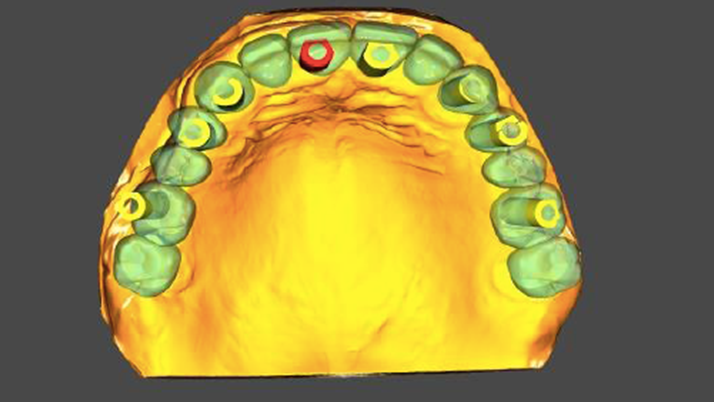

Clinical case: Extraction of all teeth in upper maxilla,

immediate implant placement, & provisionalization

- Courtesy of Dr. Iulian Filipov, Romania -

Keywords

AnyRidge, immediate placement, immediate provisionalization, maxillary fully edentulous case, initial stability, edentulous, Dr. Iulian Filipov, R2GATE, MEGA ISQ

Products:

AnyRidge implant system, Mega ISQ, R2GATE